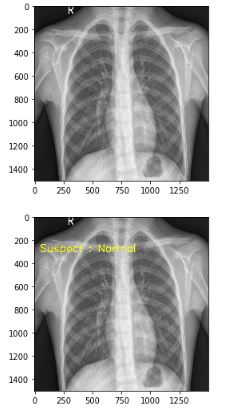

INFERENCE RESULT REVIEW

Subjek positive Subjek normal